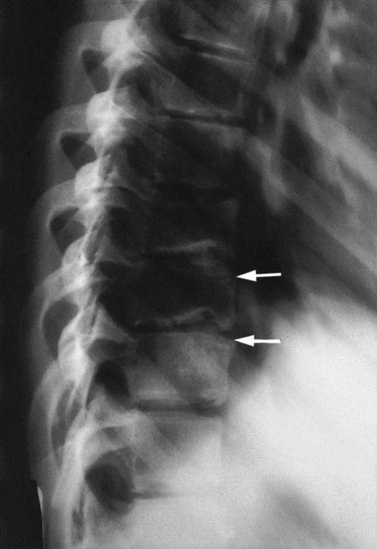

The changes in Scheuermann’s disease are primarily to the anterior margins of the thoracic vertebra as these bear greater weight. The disc narrows anteriorly, and deficient growth of the vertebral body occurs as a result of epiphyseal malformation. The vertebra gradually takes on a wedged formation. Normally, several vertebrae are affected in the thoracic spine. The athlete is usually a skeletally immature adolescent, with a ‘rounded back’ posture. In the active stage of the condition there may be localized pain, often provoked by repeated thoracic flexion as occurs in certain swimming strokes (butterflier’s back) and aerobic dance classes. Deep notches are visible over the anterior corners of the vertebrae on x-ray, and these appear sclerotic rather than rarefied (Fig. 14.18). The ring epiphyses are irregular, but the erythrocyte sedimentation rate (ESR) is normal.

image

Figure 14.18 Radiographic appearance of Scheuermann’s disease.

From Read (2000) with permission.